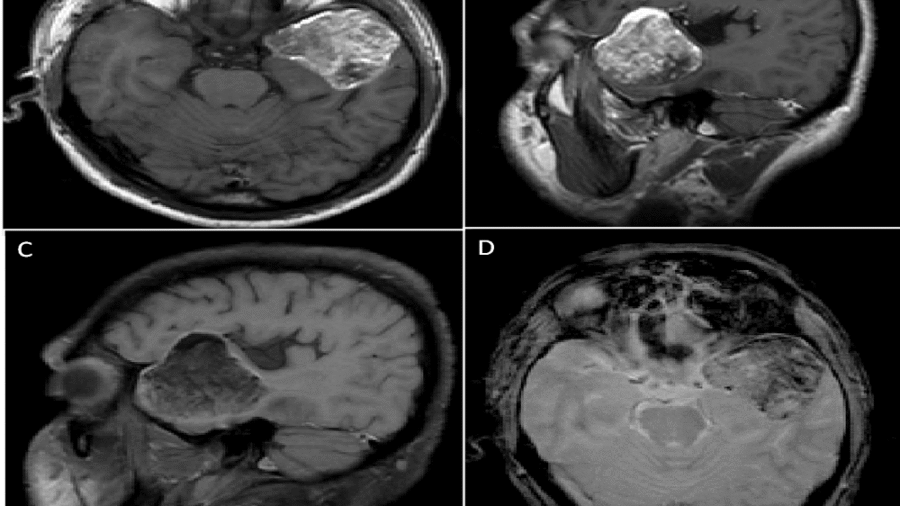

39 years , male, presented with progressive gait disturbance and speech difficulty since 11 months. Associated with headache, giddiness and vomiting since 3-4 months.